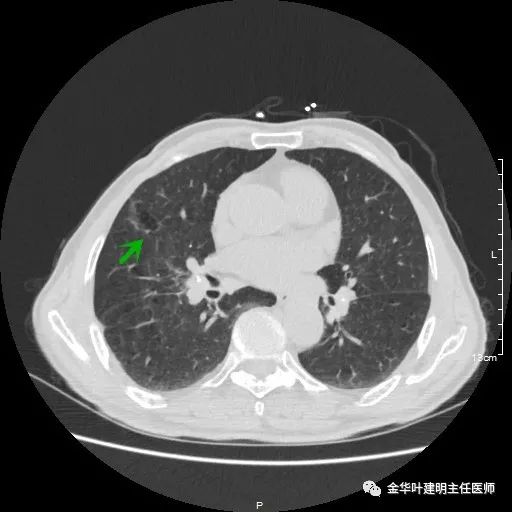

以上示右肺中叶病灶3。是混合磨玻璃结节,位置差,邻近肺门部,无法局部楔形切除,抗炎治疗后靶扫描显示了更清楚的细节,是典型的肺癌影像特征(此处未另提供)。从单病灶来看,需要行右肺中叶切除并清扫淋巴结才能得以治疗。

以上示右中叶病灶4。也是囊腔型病灶,病灶大,囊壁是磨玻璃密度,亦是较为典型的囊腔型肺癌影像。单病灶看,需中叶切除来治疗,因病灶3的存在,中叶切除可同时解决病灶3与病灶4。